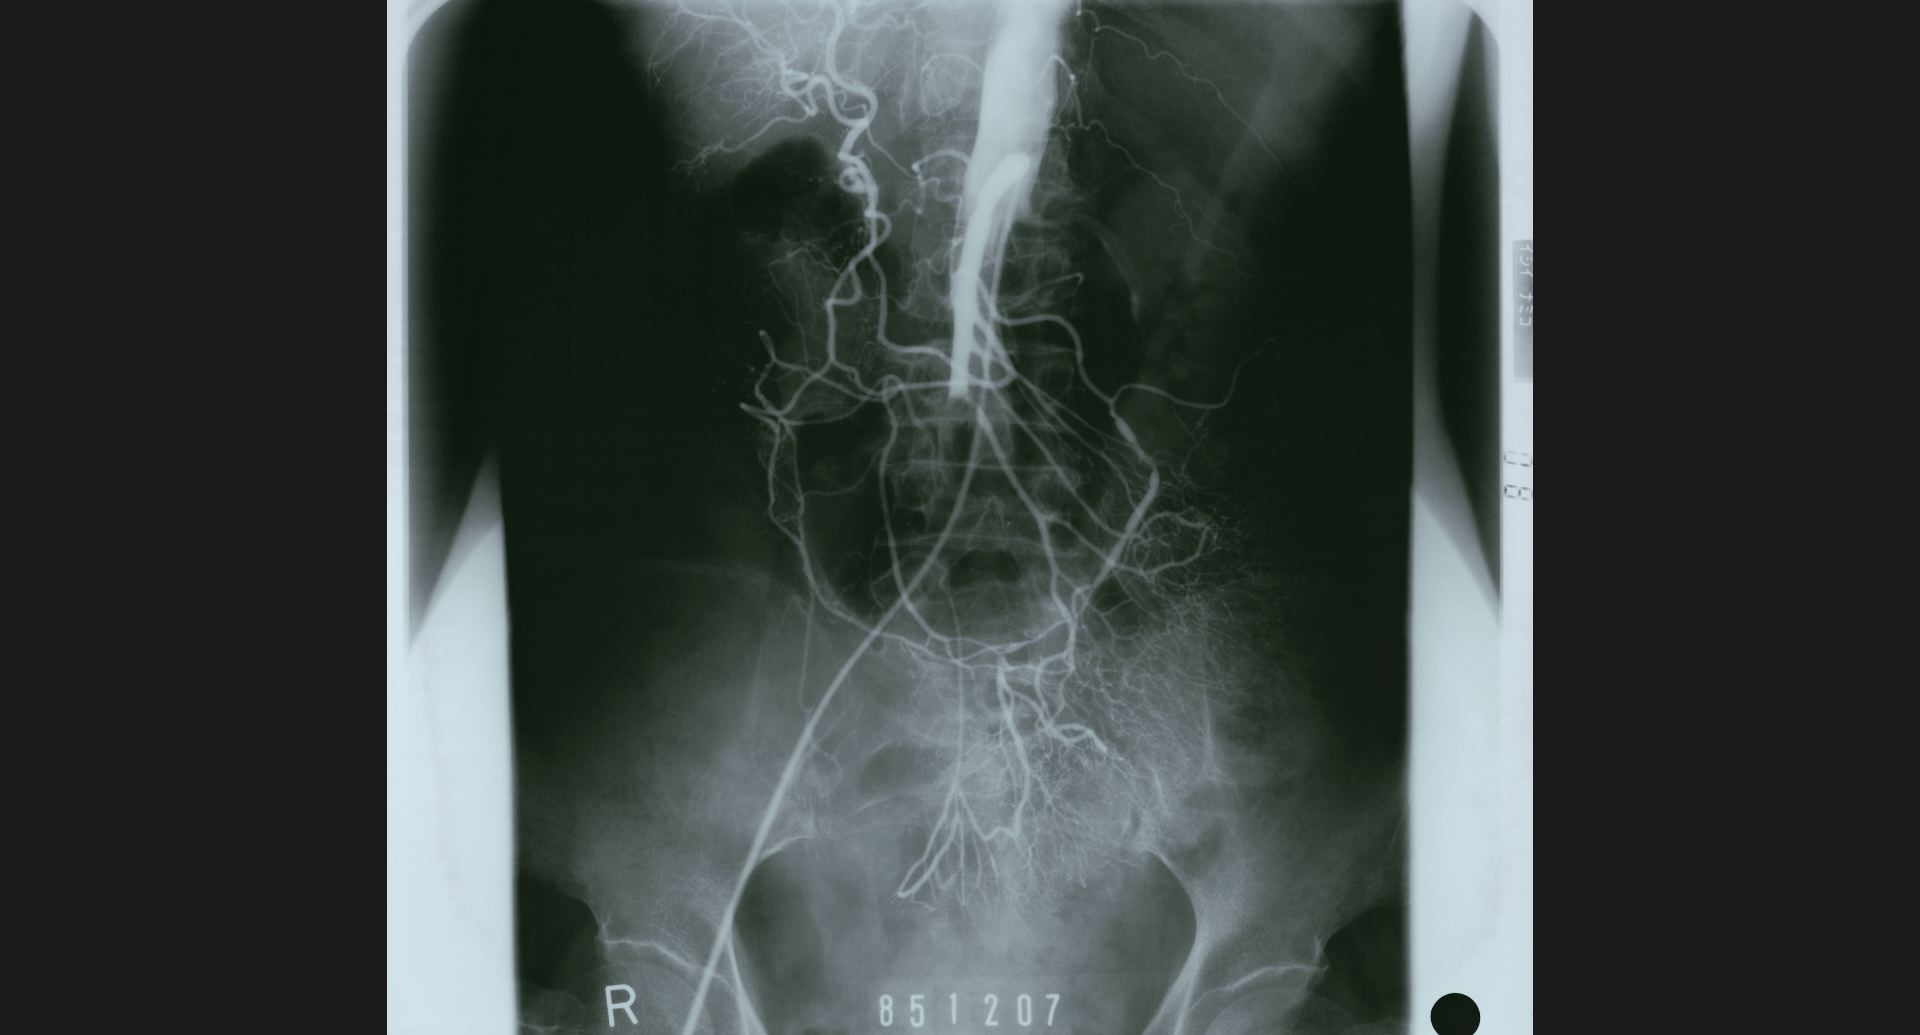

fig.13(151KB) :Aortic aneurysm (DSA)

aneurysm。正常部との境界。